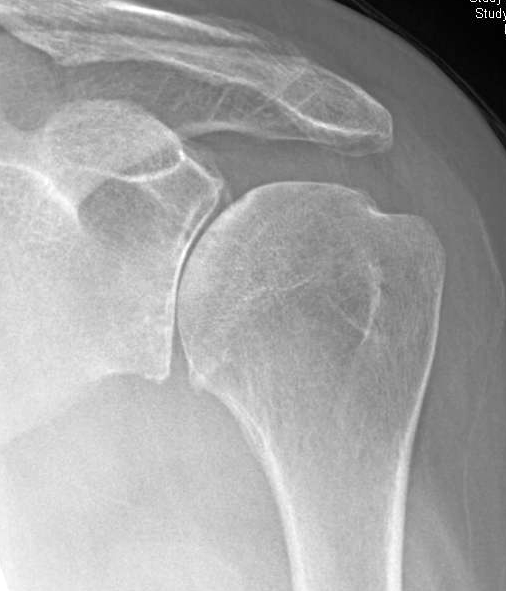

Periprosthetic fracture of the glenoid: The posterior labrum is avulsed, and stripped scapular periosteum remains attached to the posterior labrum (arrowhead).

An impaction fracture is also present at the posterior glenoid rim (blue arrow). Posterior glenoid fractures although rare can lead to recurrent instability. Operative techniques often involve a large dissection to view the fragments resulting in local soft. #posterior glenoid fracturearthroscopic fixationwe performed the surgery in lateral position with arthroscopic reduction and fixation with 2 c c screws.this. Arthroscopic posterior glenoid fracture fixation using knotless suture anchors. Posterior dislocations are uncommon and easily missed, because there is less displacement compared to the anterior dislocation. Shoulder instability after a posterior glenoid rim fracture is rare and potentially difficult pathology to treat. Or incomplete neck fracture top. Etiology, natural history, anatomy, clinical evaluation, xray / diagnostic tests glenoid fracture clinical evaluation. Arthroscopic fixation of posterior glenoid fracture подробнее. Shoulder instability after a posterior glenoid rim fracture is rare and potentially difficult pathology to we describe an arthroscopic technique for posterior glenoid rim fracture fixation using knotless. Classification of glenoid cavity fractures: • fracture of the base of the coracoid process and glenoid neck fracture • glenoid cavity fracture and disruption of the superior shoulder suspensory complex slight retraction and posterior rotation of the arthroscope will allow examination of the posterior. Glenoid fracture exits at lateral. (obq08.134) the modified judet approach to the posterior scapula exploits the internervous interval between what two muscles? Impaction fracture of anteromedial humeral head. Isolate fracture of lesser tuberosity.